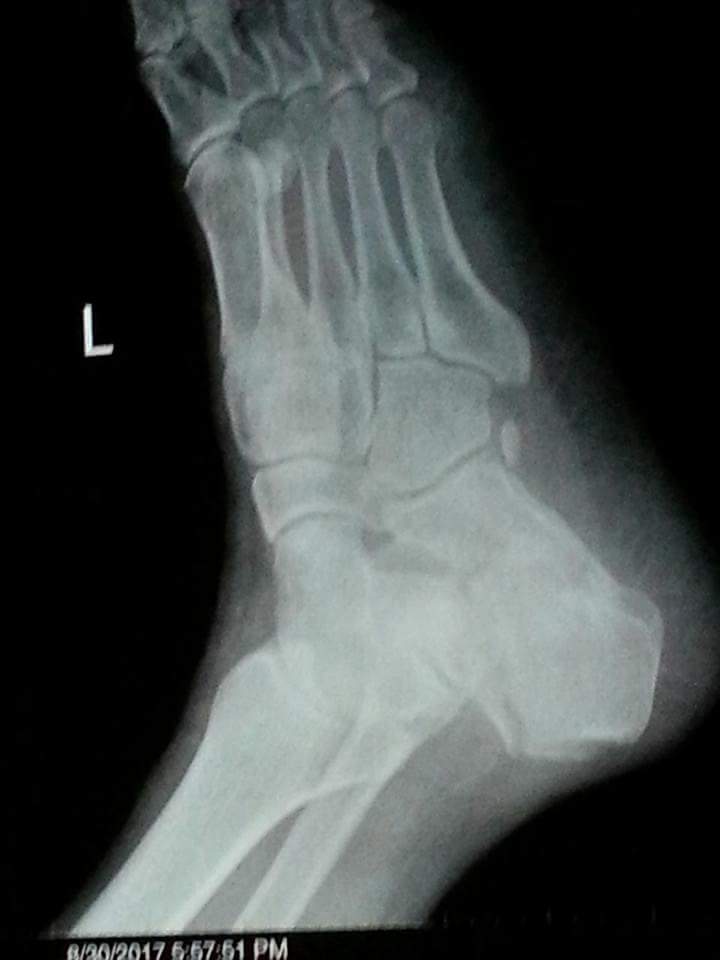

My father fell off from height 3 weeks back and got his left calcaneus fractured. We saw a doctor the same day who applied plaster cast on his foot and adviced icing and foot elevation Later, we saw another doctor who adviced cast removal immediately and starting physiotherapy and exercises. The latter also said that cast should not have been applied in this particular case. Also, the cast application on the same day of fracture could cause ischemia due to impending swelling.

this fracture need surgery for better functional outcome

This needs surgery